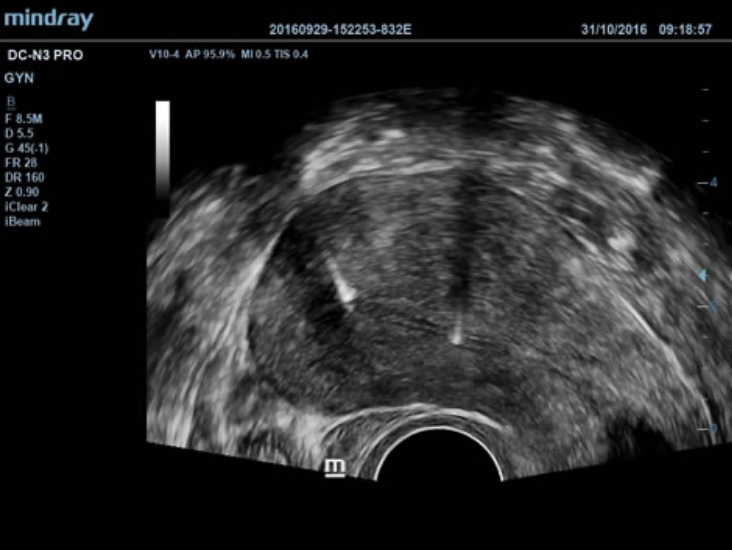

PSH? (Phase Shift Harmonic Imaging)

Purified Harmonic Imaging (Pencitraan Harmonis yang Dimurnikan) agar resolusi kontras lebih baik, memberikan gambar yang lebih jelas dengan resolusi luar biasa dan minim noise.